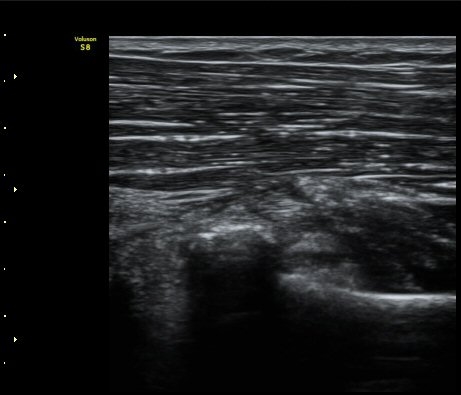

ÆÈ²ÞÄ¡  ¾ÕÂÊ¿¡¼­ ½ÃÇàÇÑ ¿ä°ñµÎ Á¾´Ü¸é°Ë»ç¿¡¼­ ƯÀÌ ¼Ò°ßÀ» º¸ÀÌÁö ¾ÊÀ½(±×¸² 1).